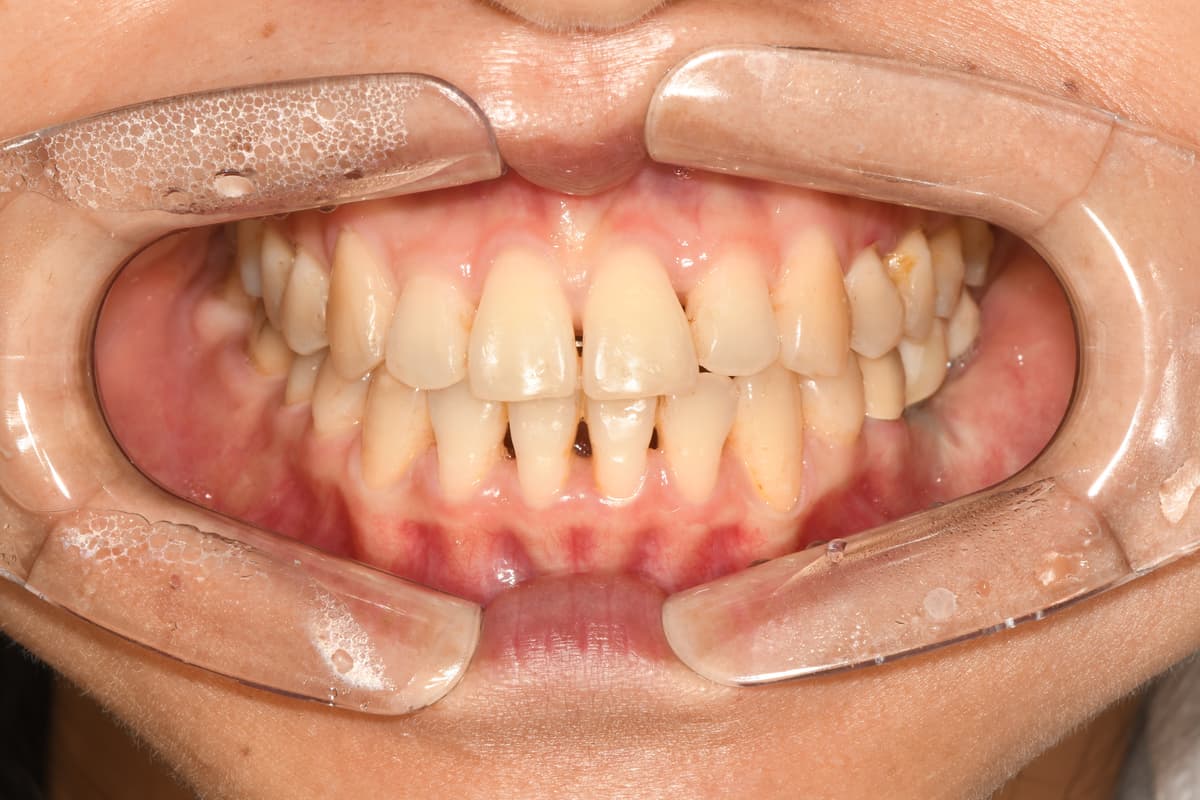

교정 치료 전후 사례

교정과 전문의가 직접 진료한

실제 환자 케이스입니다

김●● · 일반 교정